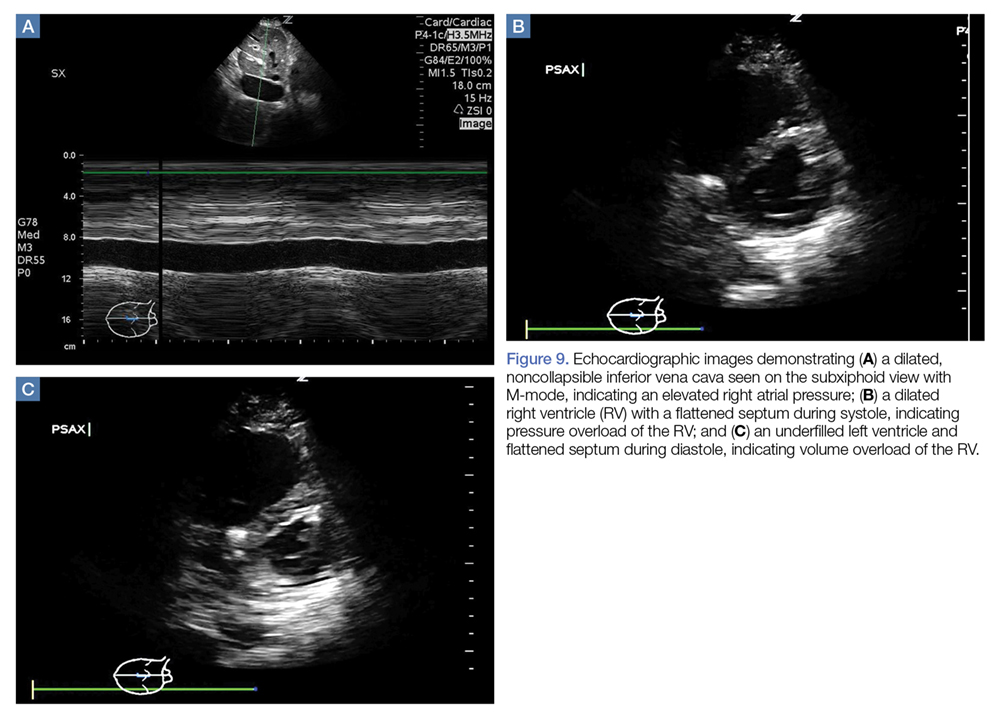

Right Ventricular Pressure/Volume Overload

While inferior vena cava (IVC) ultrasound has been shown to be a pre-heart/lung assessment of cardiopulmonary interactions that predicts volume responsiveness, the IVC is also a good predictor of right atrial (RA) pressure. 35 If the IVC is dilated and lacks respiratory variation, the patient likely has an elevated RA pressure, which is most likely transmitted from an elevated RV pressure ( Figure 9a ). However, compliance of the RA, RA pressure and, by extension, IVC prediction of that RA pressure, may underestimate the degree of RV pressure or afterload.

Figure 9.

In the presence of pressure overload of the RV, septal motion will be toward the LV and flatten during systole ( Figure 9b ). Despite movement of the septum toward the LV on systole, the LV is still able to fill in diastole and maintain an adequate cardiac output (often with concomitant tachycardia). When the RV is volume-overloaded, the septum flattens on diastole, which has a more deleterious effect on cardiac output ( Figure 9c ). Due to pericardial restraint on the free wall of the LV, the LV is unable to fill during diastole and thus cardiac output drops. 30,36 The well-known “D-sign” occurs when the RV is both pressure- and volume-overloaded, which often occurs when a hypotensive patient with a pressure-overloaded RV receives a bolus of fluid. McConnell’s sign occurs when the pressure and volume-overloaded RV has apical “blinking” caused by tethering of the shared muscle fibers with the LV. 37